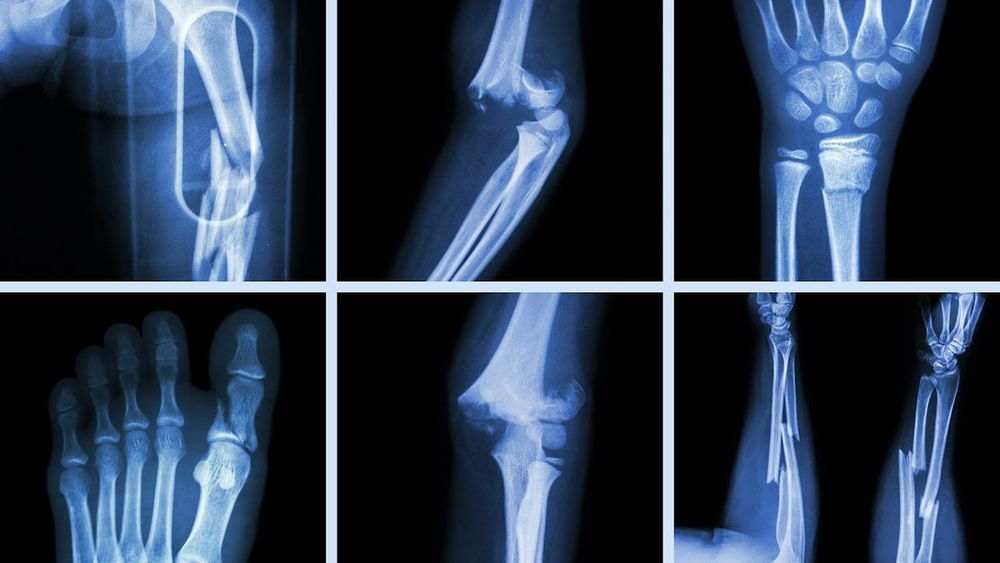

तसं पाहायचं तर फ्रॅक्चर म्हणजे हाड मोडणे हा बऱ्यापैकी सामान्य असलेला प्रकार आहे. सर्वसाधारण मनुष्याला आयुष्यात सरासरी दोन वेळा फ्रॅक्चरला सामोरे जावे लागते. जेव्हा हाडाला त्या हाडापेक्षा जास्त शक्तिशाली वस्तूमुळे इजा होते तेव्हा हाड मोडते. फ्रॅक्चर होण्याचा धोका वयाबरोबर वाढत जातो. खरेतर लहान मुलांमध्ये खेळताना पडल्यामुळे अनेक वेळा फ्रॅक्चर होत असते. परंतु लहान मुलांमध्ये होणारी फ्रॅक्चर्स कमी गुंतागुंतीची असतात. जसजसे वय वाढत जाते तसतशी हाडे ठिसूळ होत जातात आणि त्यामुळे फ्रॅक्चर होण्याची शक्यताही वाढते.